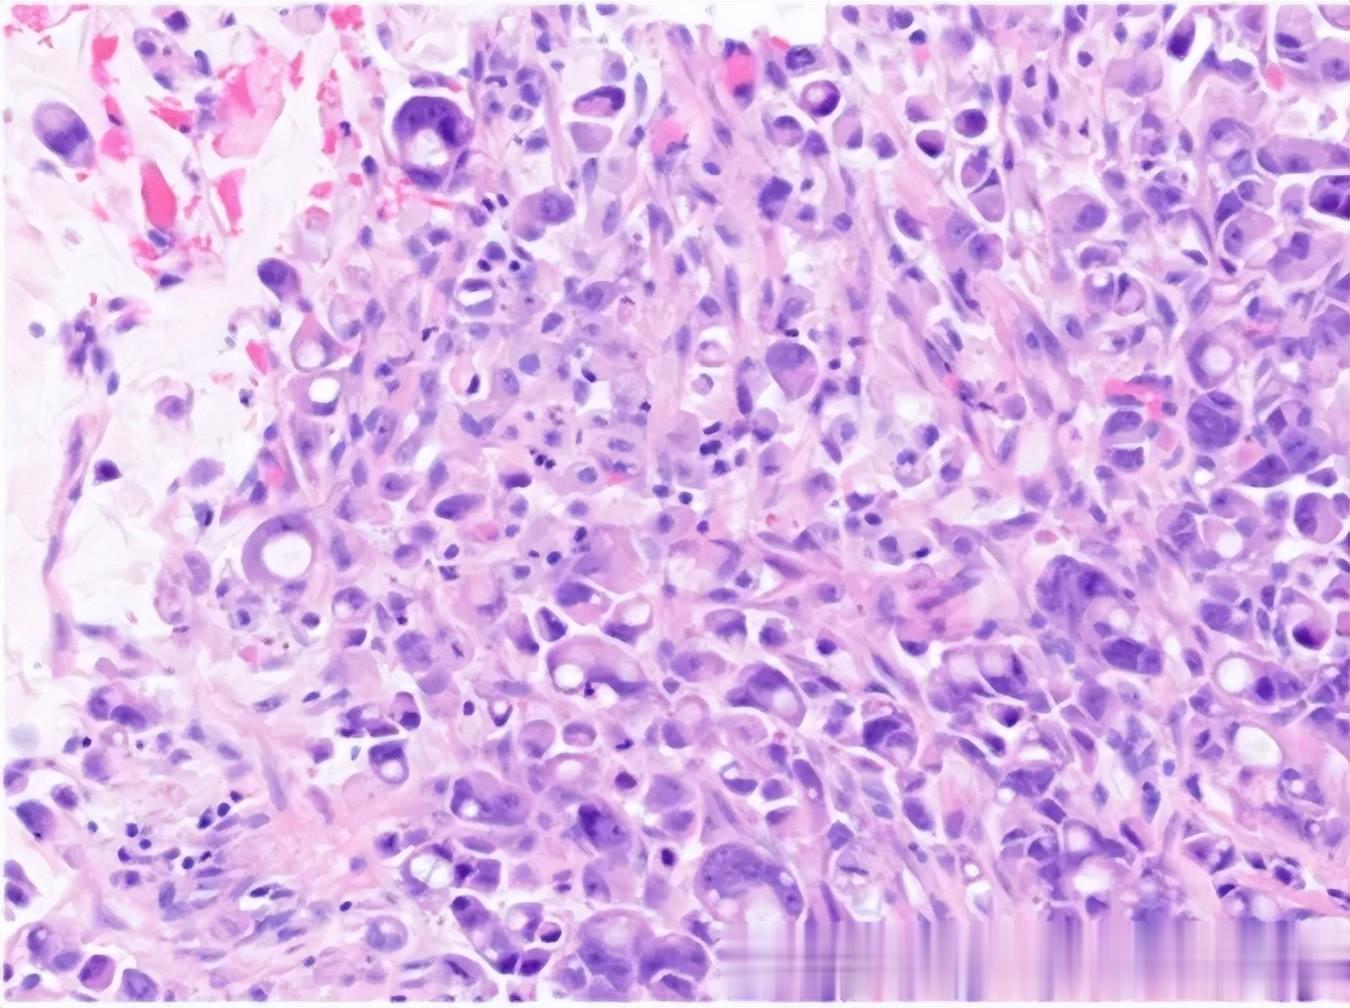

*术后病理诊断:胆囊壁可见低分化腺癌弥漫浸润,呈低粘附性癌表现,局灶呈印戒细胞癌,肿瘤大小约3.2×2×1.5cm,浸润胆囊壁全层,可见广泛神经周围侵犯,未见明确脉管内癌栓。

(▲ 胆囊印戒细胞癌)